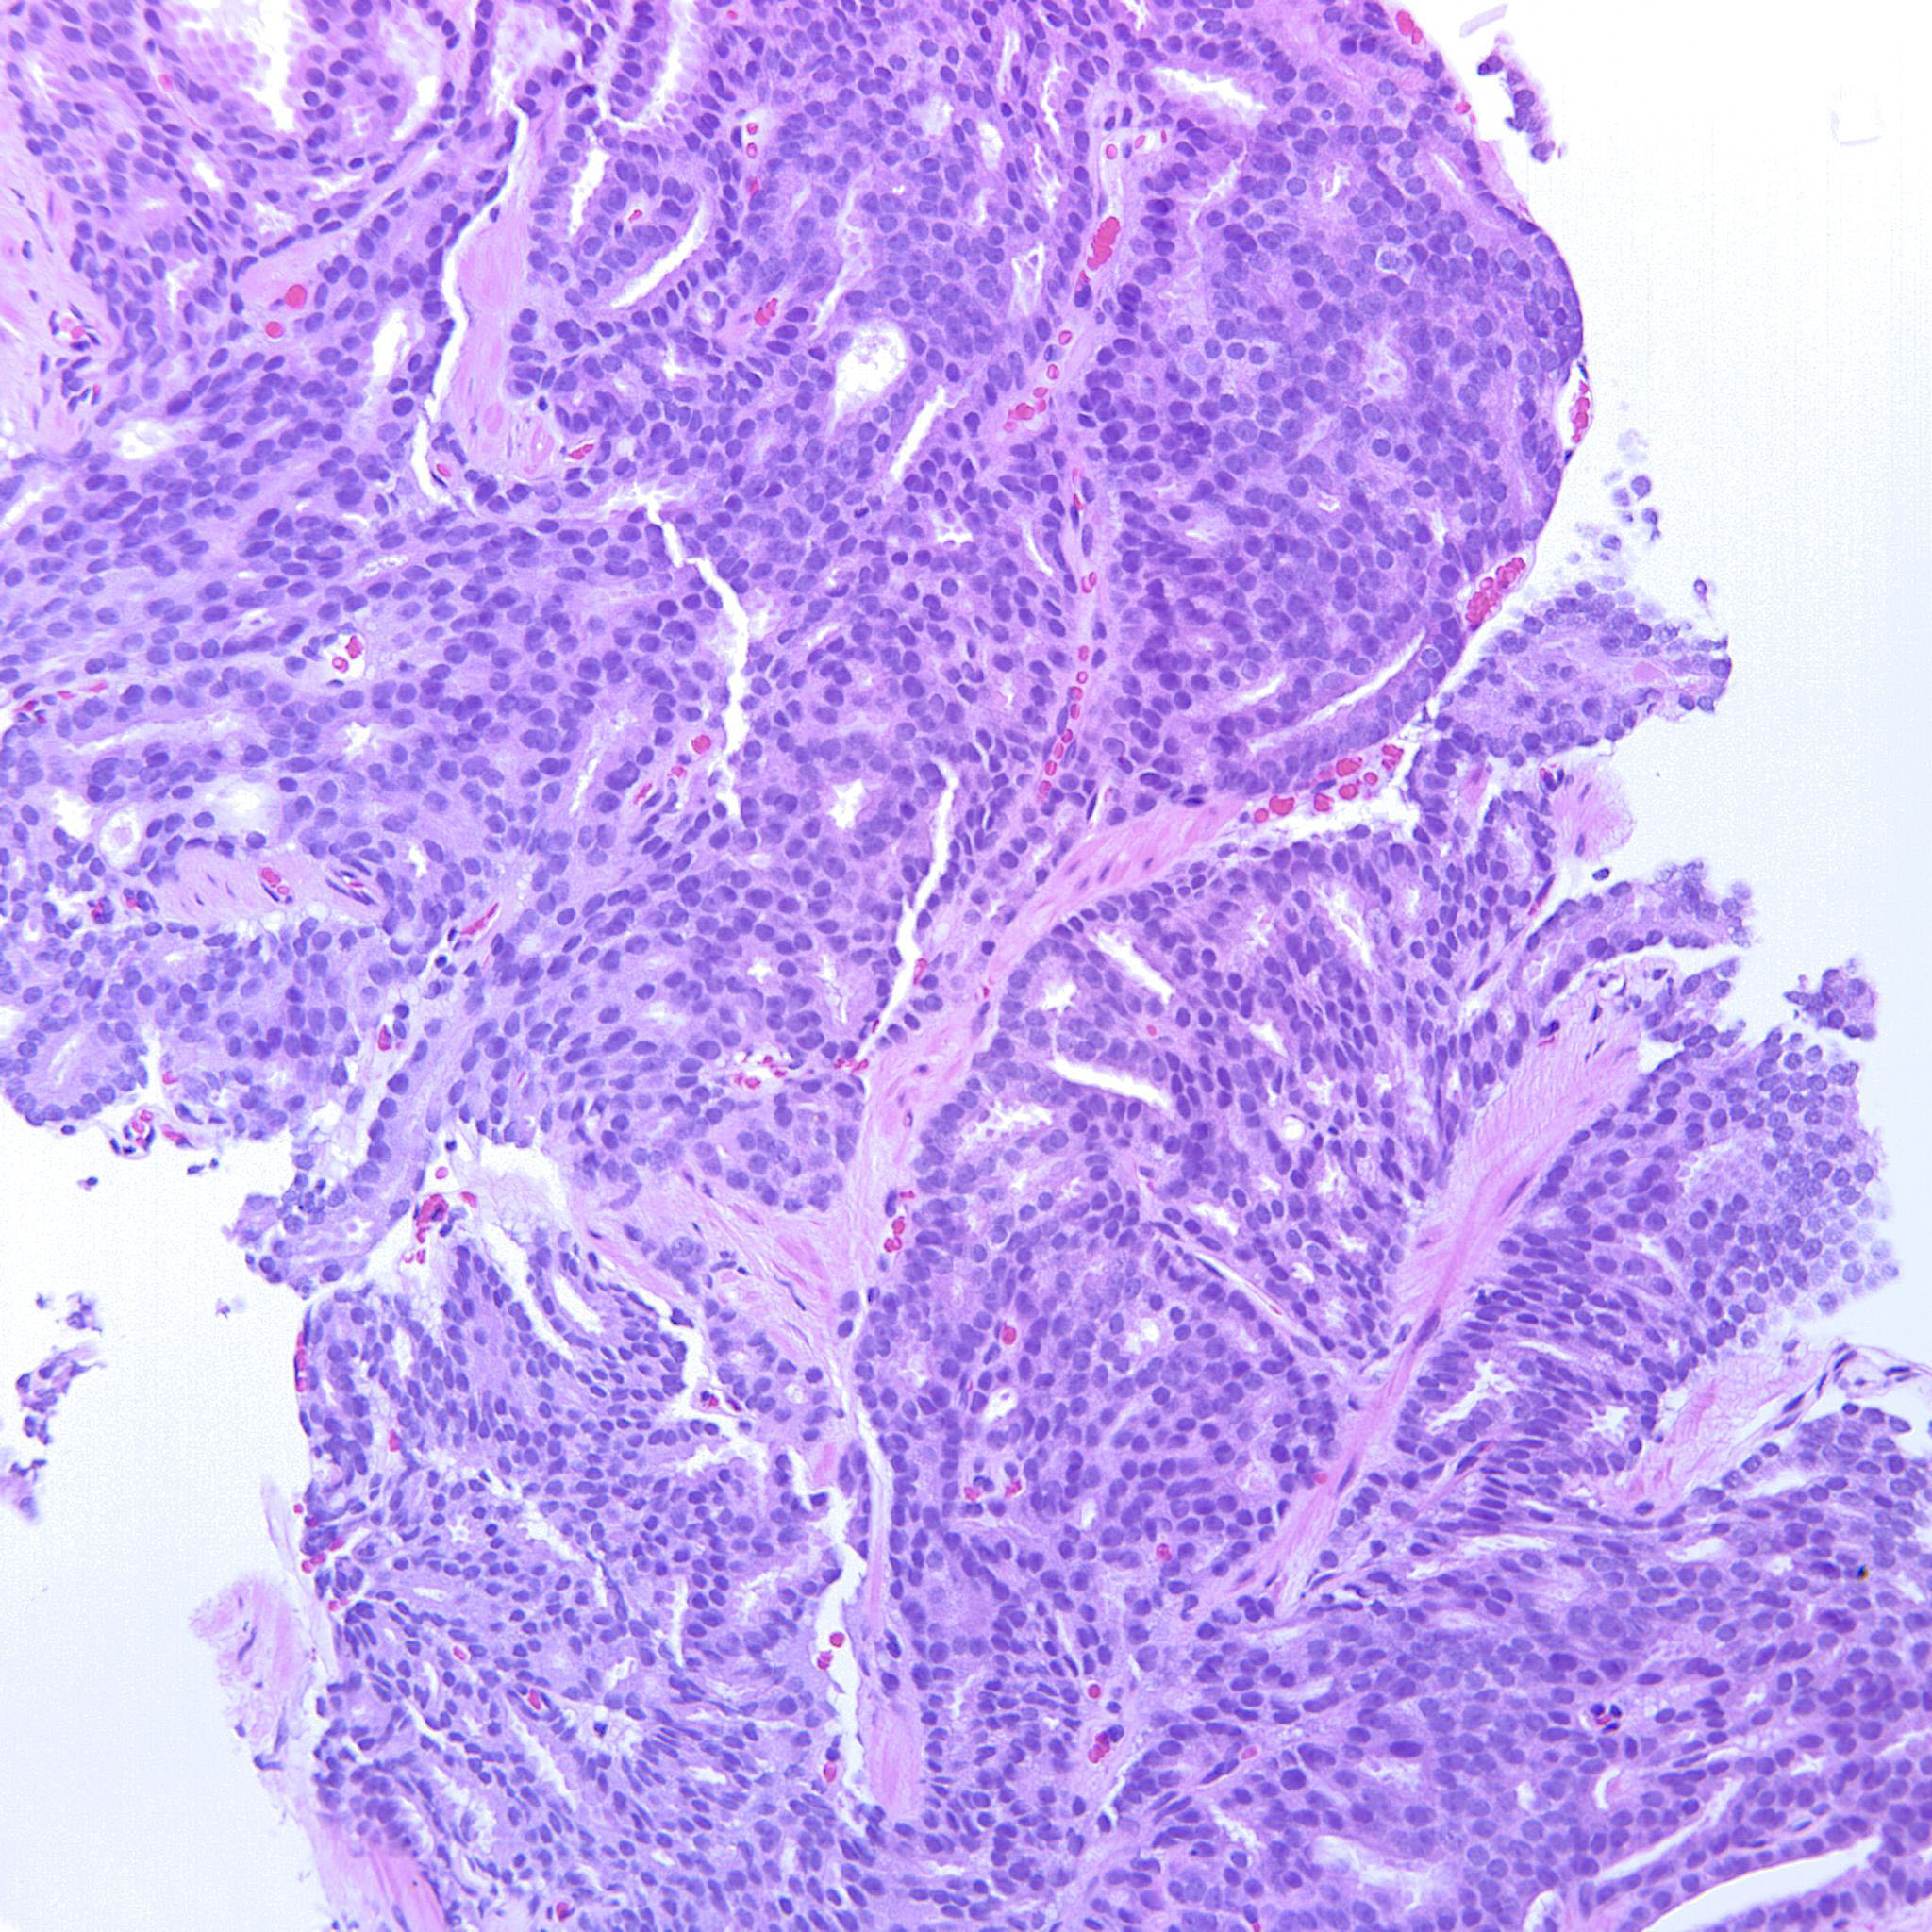

Prostate cancer grading

Case ID: 227